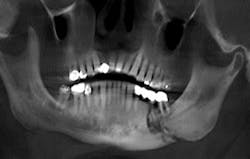

The presence of exposed bone may be subtle and may at first appear as a fistula or periodontal defect when probing, or granulation tissue covering over unhealed exposed bone.3 In reviewing the database from the University of Miami, 29% of cases of exposed bone develop spontaneously without any initiating insult to the alveolar bone, and 61.6% are initiated by extraction. Dental implant surgery accounts for 2.2%, bone biopsy 1.1%, and periapical surgery is an initiating event in only 0.5% of cases.3 Affected alveolar bone is often seen by observing sclerosis of the lamina dura in a radiograph or radiographic identification of a more diffuse sclerosis in the alveolar bone.3